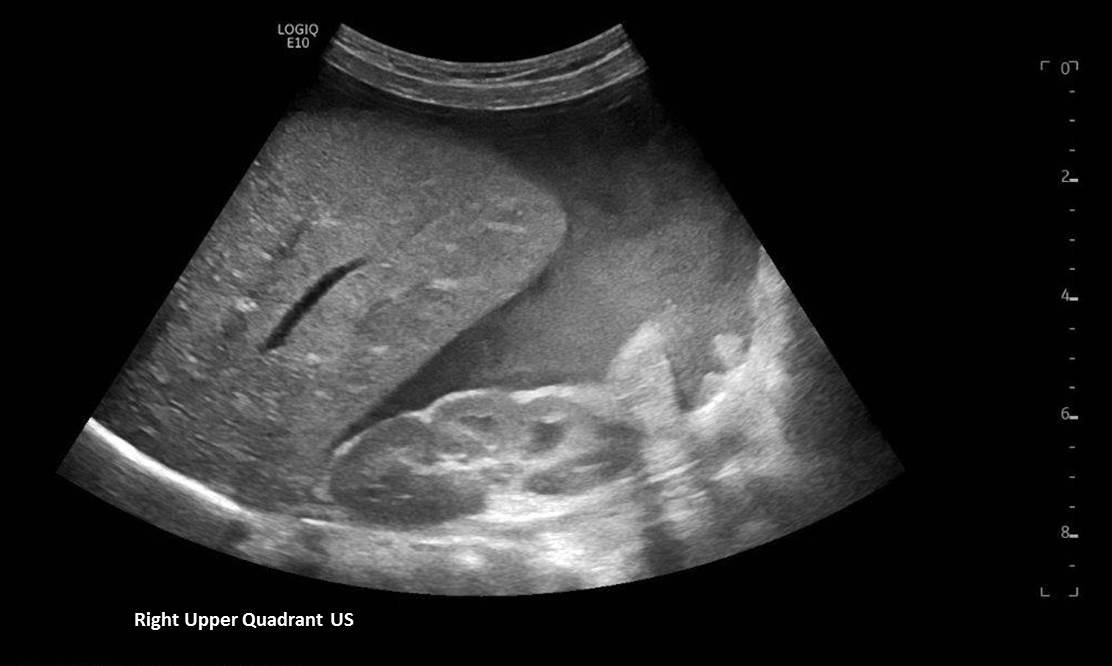

A 5-month-old female presented to the emergency department with worsening abdominal distention and postprandial emesis. Point-of-care ultrasound (POCUS) demonstrated extensive abdominal free fluid with a large, heterogeneous mass in the suprapubic region. This was confirmed on computed tomography (CT) of the abdomen and pelvis. The patient was urgently taken to the operating room for exploratory laparotomy where a ruptured tumor was discovered. The patient was eventually diagnosed with ovarian juvenile granulosa cell tumor. POCUS can be vital in guiding the recognition of rare pediatric conditions in the emergency department and should be considered in patients where there is concern for an acute abdomen.